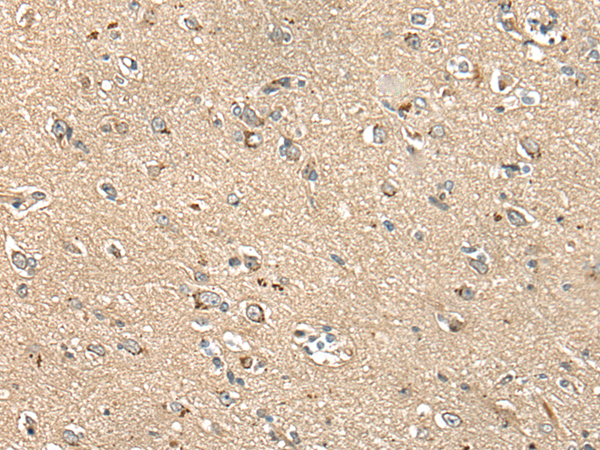

分类: 科研抗体货号: P02429别名: C1orf93; FAM213B应用: WB,IHC反应种属: Human, Mouse, Rat